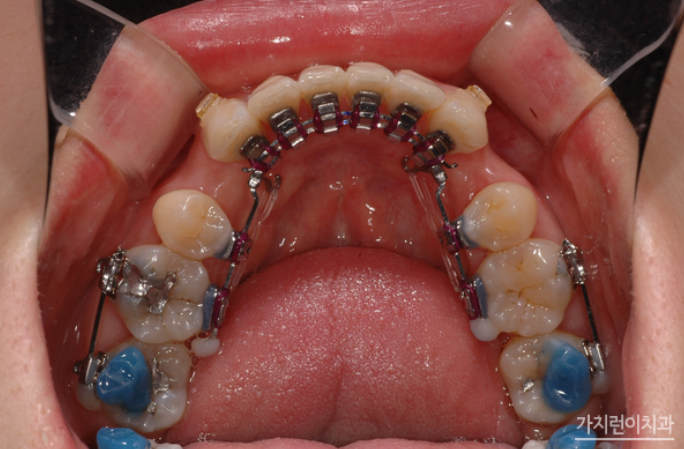

더블와이어 설측탄댐장치란!?

위 사진은 더블와이어를 이용한 설측탄댐장치인데요. 치아의 비뚤어짐이나 쓰러짐, 뿌리 조절 등을 정교하게 컨트롤할 수 있는 교정장치입니다. 3차원적인 치아이동 조절을 위해 특수하게 고안된 장치인데요. 기존의 설측교정장치가 뿌리 이동이 용이하지 않았다는 단점을 개선해 미세한 조절이 가능해졌다는 특징이 있습니다.